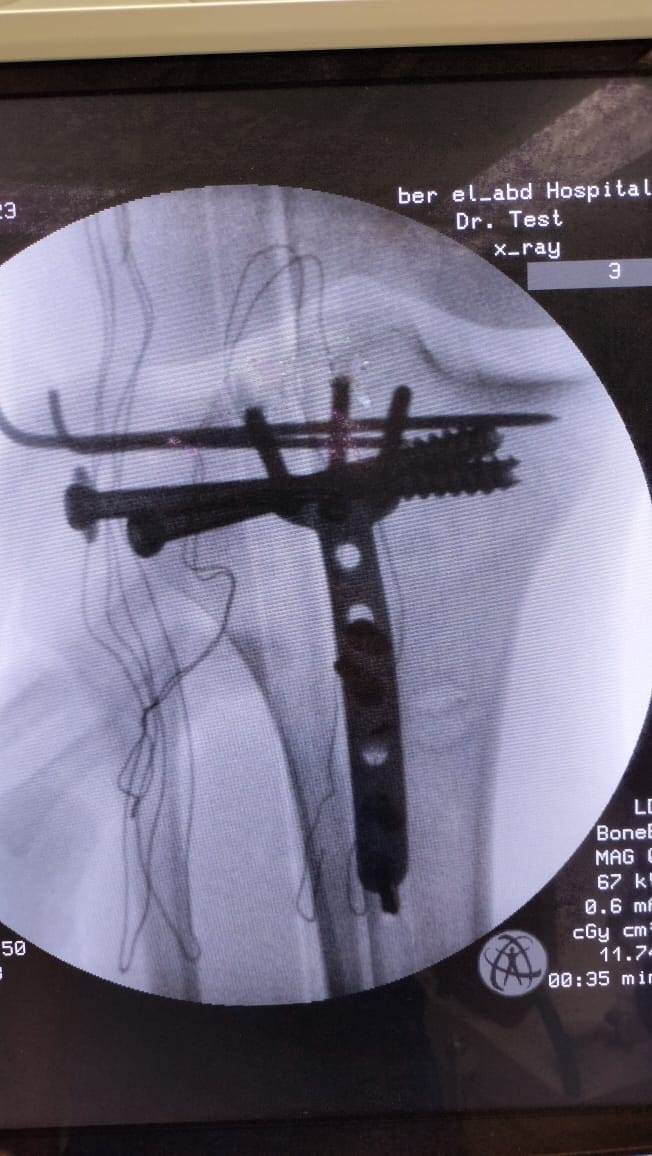

مشيرًا الى أن ذلك النوع من الكسور يكون قريبًا جدًا من الأعصاب والأوعية الدموية الرئيسية للساق والتي توجد خلف مفصل الركبة.. حيث تم الوصول الى الكسر وإعادة بناء سطح المفصل وتثبيته باستخدام شريحة ومسامير وأسلاك معدنية باستخدام جرح ٧ سنتيمترات خلف الركبة واستخدام مسامير جانبية مجوفة بدون فتح لتثبيت الجزء الخارجى من سطح المفصل، وتم الاطمئنان على الأوعية الدموية قبل إفاقة المريض، وبعد تمام الإفاقة.. تم الاطمئنان على الأعصاب والأوعية للمريض.

وأضاف أنه نظرًا لقرب هذا الكسر من سطح المفصل تم عمل أشعة مقطعية بعد الجراحة للتأكد من جودة بناء المفصل وعدم وجود أى بروز للمسامير داخل المفصل، وجارٍ تحضير المريض لعمل رنين مغناطيسى لتحديد الأربطة الداخلية والخارجية للركبة التي ستحتاج لإعادة بناء بالمنظار.